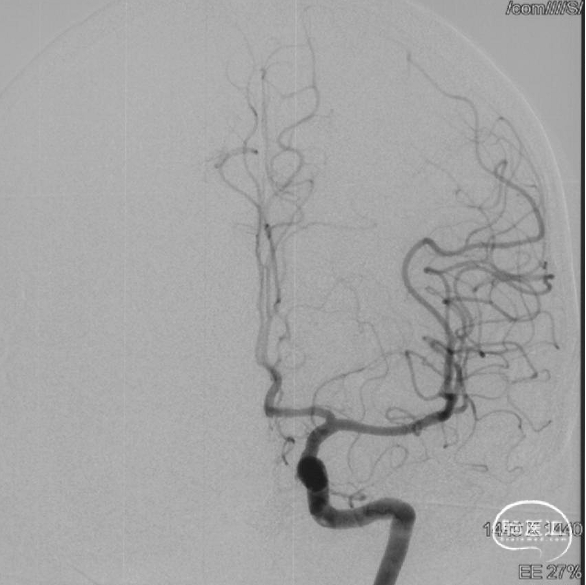

最终造影瘘口完全不显影。

双侧脉络膜染色正常。

术后三个月造影复查,双侧颈内动脉、颈外动脉造影均未见静脉早显,DAVF治愈。